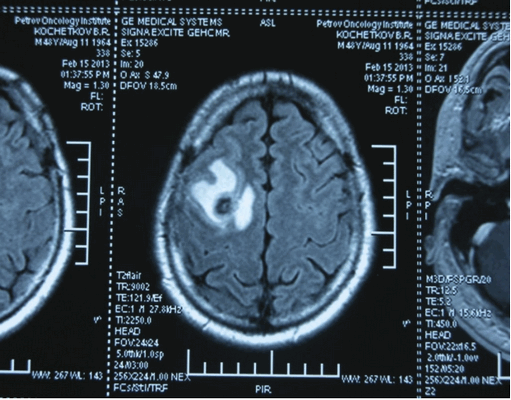

Головной мозг

Герминогенные новообразования в данной области - это примерно 2-4% от всех внутричерепных (интракраниальных). Патология в 75% случаев диагностируется у мальчиков, за исключением турецкого седла, где новообразования в основном локализуются у девочек.

Герминомы формируют инфильтрирующие опухоли больших размеров, часто являющиеся источниками субарахноидальных (между мягкой и паутинной оболочками мозга) и вентрикулярных (желудочковых) метастаз.

Рисунок 7. - Герминома головного мозга.

- КТ (расшифровка: компьютерная томография), МРТ (расшифровка: магнитно-резонансная томография), ПЭТ-КТ (расшифровка: позитронно-эмиссионная томография, совмещенная с КТ). Эти обследования необходимы, чтобы рассмотреть структуры организма послойно и визуализировать опухоль. Они показывают, как сильно распространен патологический опухолевый процесс на находящиеся рядом ткани и органы, есть ли поражение костей. КТ - это самый чувствительный метод для обнаружения метастазов в легких. Проведение МРТ и КТ головного мозга необходимо, чтобы обнаружить и визуализировать герминогенные новообразования эпифиза.

Рисунок 9. - метастаз в головной мозг при герминогенной опухоли.